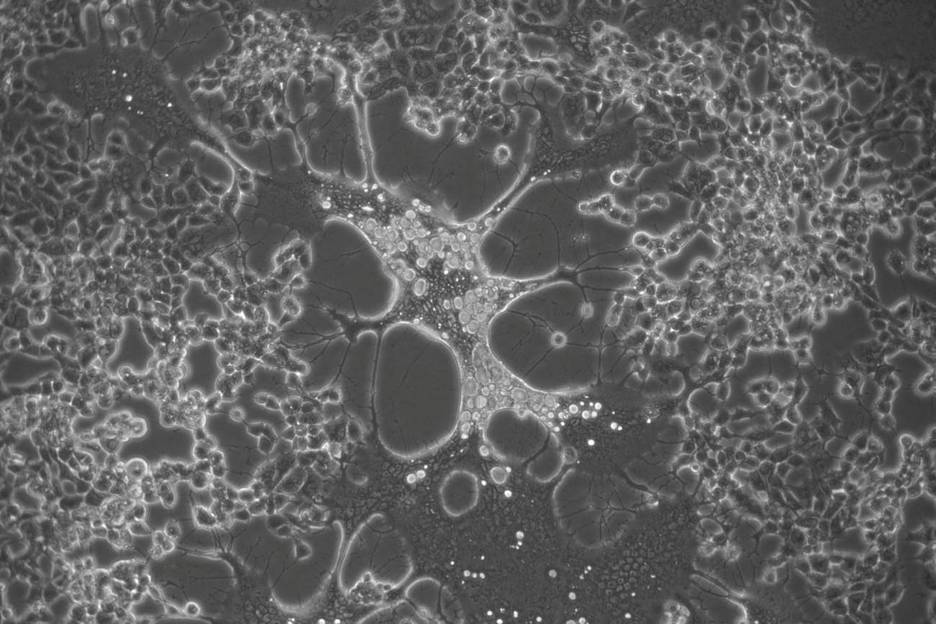

“El virus del herpes simple es uno de los patógenos humanos más prevalentes a escala mundial, para el cual no existe cura o vacuna. Hemos encontrado que ambos tipos de herpes simplex acumulan cambios cuando replican en cultivo celular, lo que puede cambiar su fenotipo muy rápidamente”, explica Antonio Alcamí, del Centro de Biología Molecular Severo Ochoa (CBM-CSIC-UAM), centro mixto del CSIC y la Universidad Autónoma de Madrid.

Estos resultados son fruto de la optimización de análisis bioinformáticos y de técnicas de ultrasecuenciación masiva, que son fundamentales para entender la forma en la que estos patógenos humanos evolucionan durante la replicación viral en diferentes tejidos.

“Hemos optimizado un método que permite detectar mutaciones nuevas que aparecen con muy baja frecuencia en la población viral cuando estos virus replican. Gracias a ello, observamos cómo el virus del herpes simplex tipo 2 genera muchas más mutaciones al replicar que su homólogo labial (tipo 1), lo que se traduce en una tasa evolutiva más rápida para el primero”, concluye Alberto Domingo López Muñoz, del Instituto Americano de Alergias y Enfermedades Infecciosas.